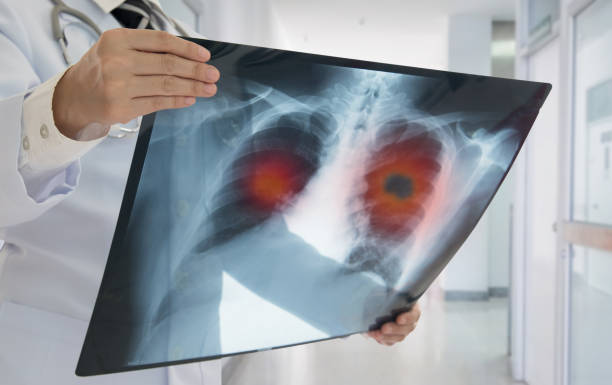

폐암 예방

폐암 예방은 궁극적으로 폐암의 원인을 차단하는 것이며, 흡연자라면 기본적으로 금연을 해야 합니다. 아울러한 최근 여성의 폐암 발병률이 증가하고 있는데 아무래도 가스레인지를 통해 폐에 유해 물질이 들어가는 경우가 많기 때문입니다. 따라서 가족력이 있는 사람은 남녀를 가리지 말고 정기적으로 건강 검진을 받아야 하며 가족력이 없다 하더라도 주의를 기울이고 정기적인 건강 검진을 받는 것이 좋습니다.